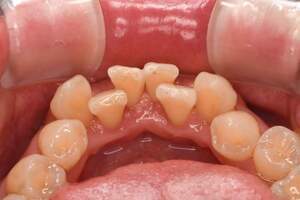

歯石除去

治療前

治療後

| 年齢 | 36歳・男性 |

| 主訴 | 歯石をとりたい |

| 治療内容 | 歯石除去 |

| 治療期間 | 30分 |

| 費用 | 約2,000円 |

| リスク・副作用 | ・歯ぐきの炎症が強いと歯石を取る際に出血することがあります。 ・処置後に歯がしみることがあります。 ・歯と歯の間に隙間ができるので、息が漏れ発音しにくいと感じることがあります。 ・歯ぐきの炎症が軽減すると歯ぐきが引き締まり、歯が長く見えることがあります。 |